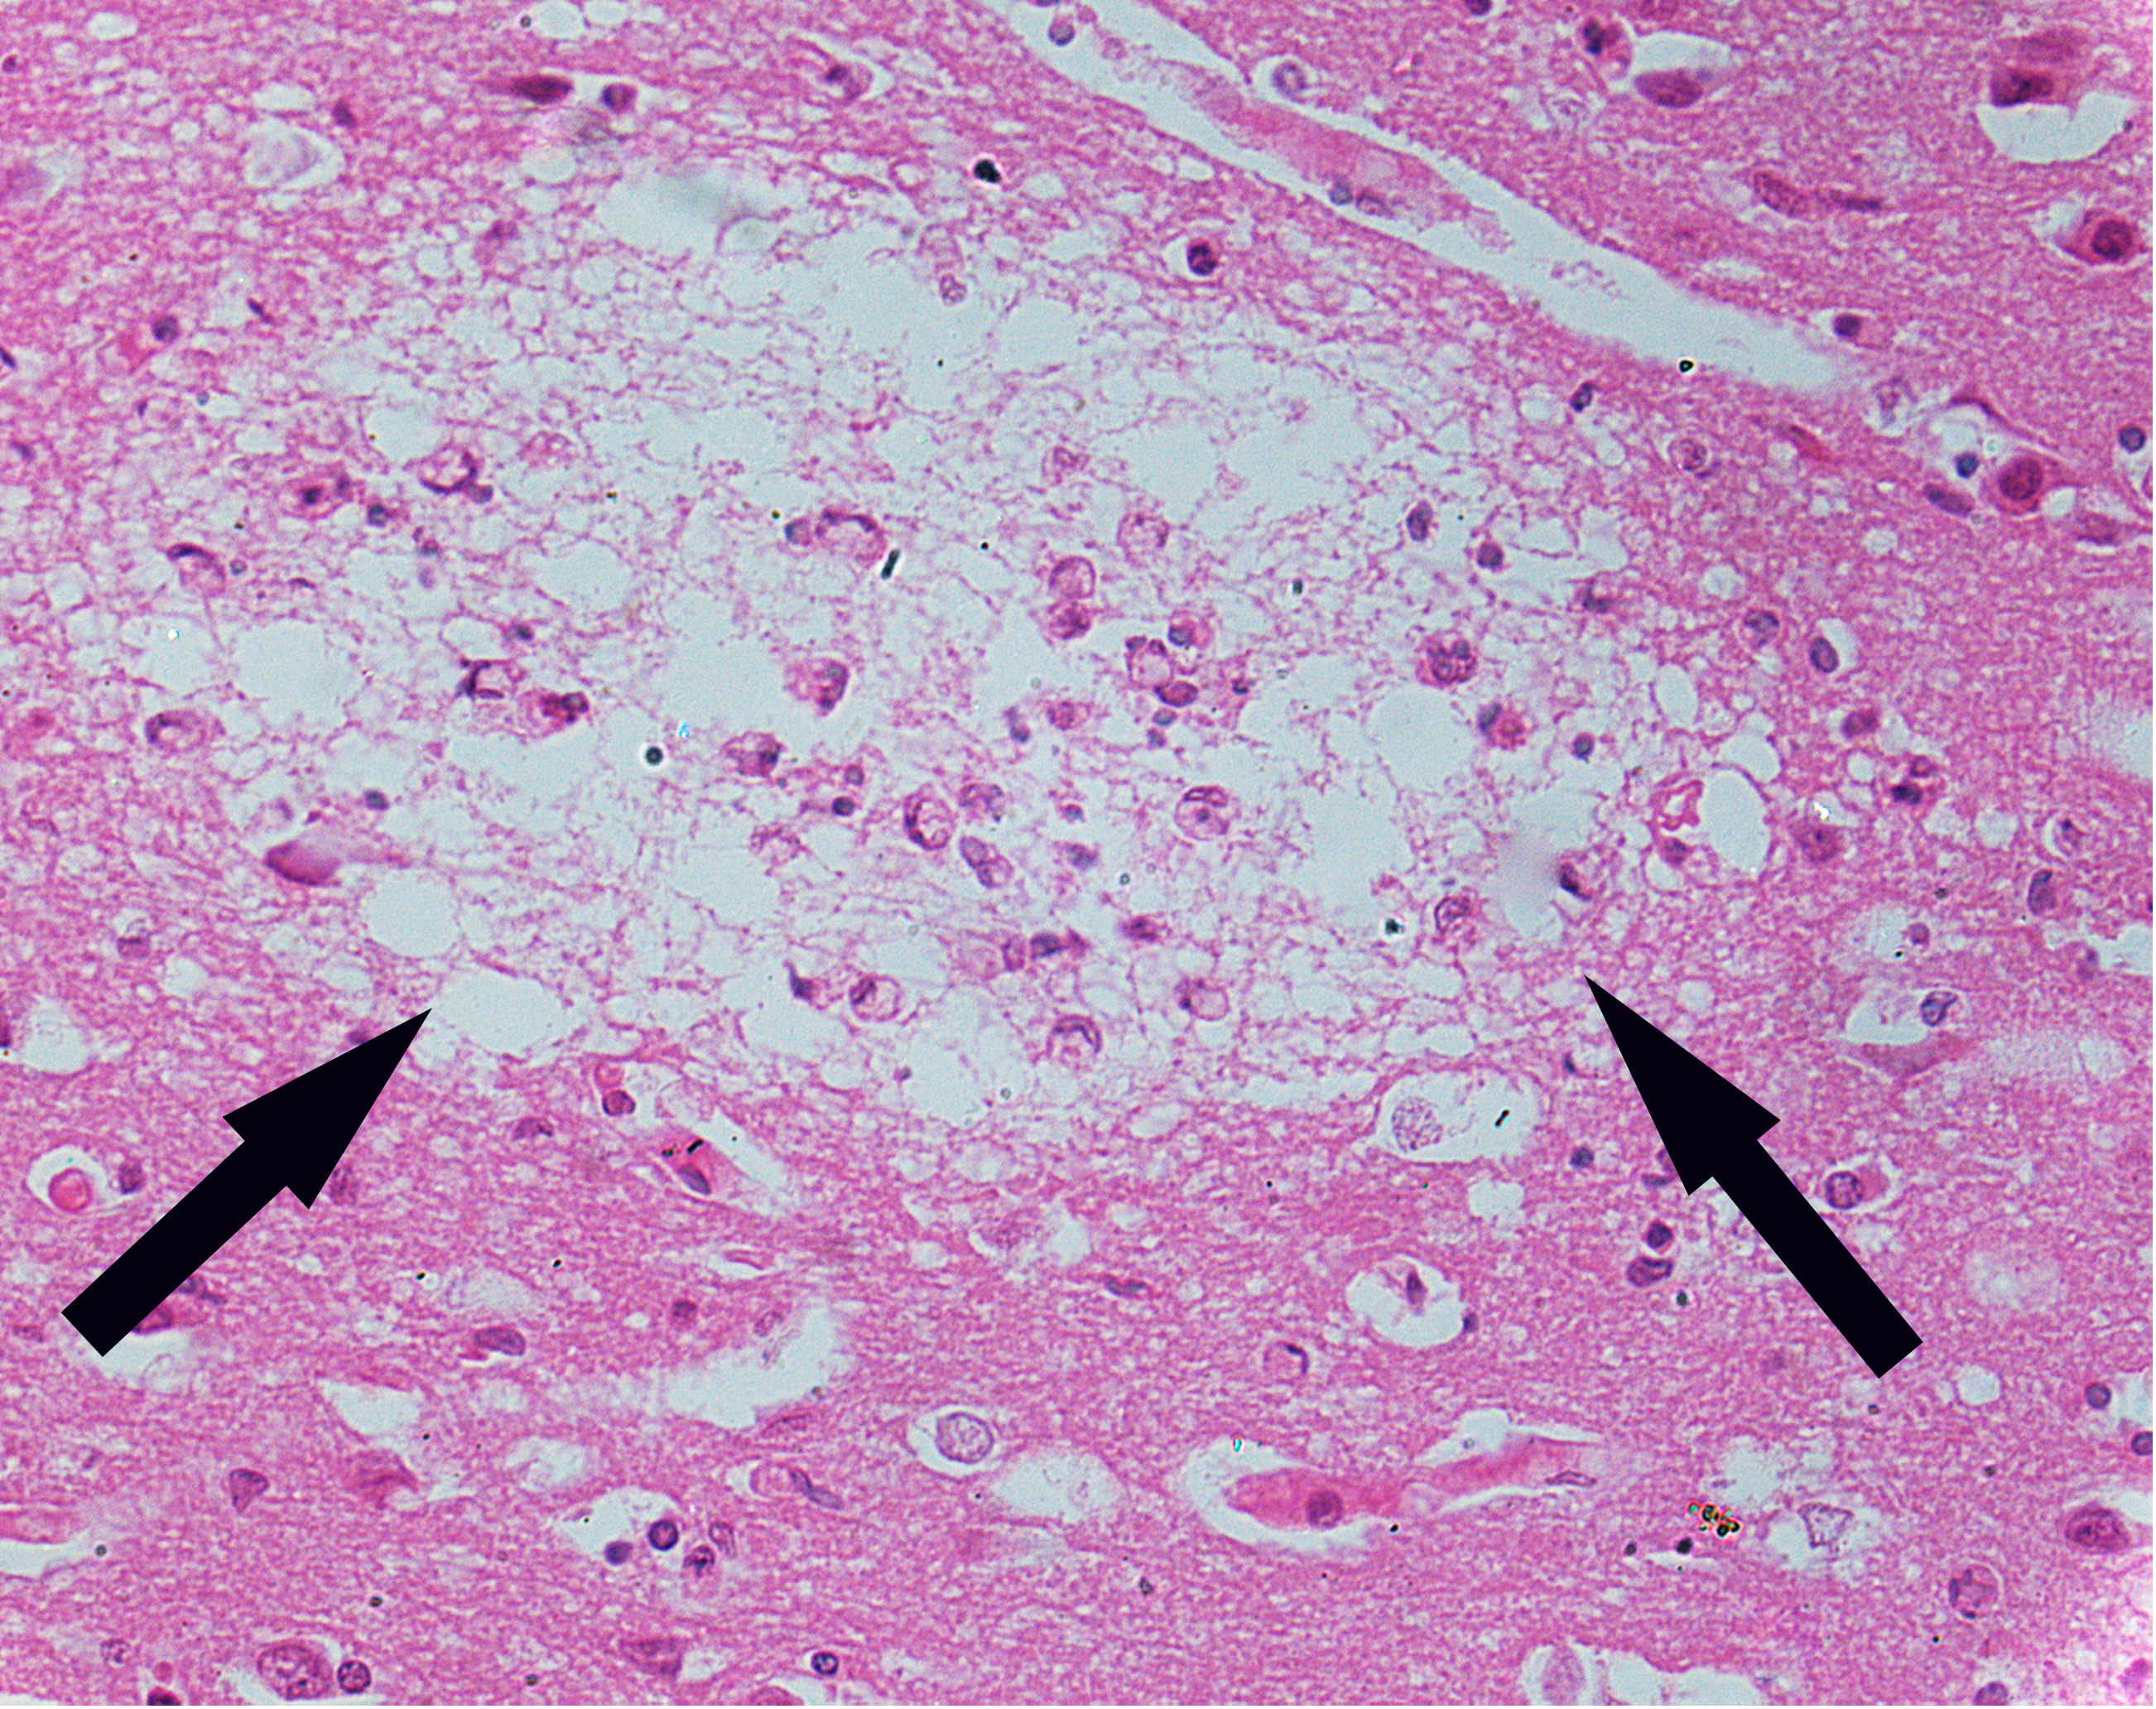

2.Encephalitis type B-liquefied necrosis